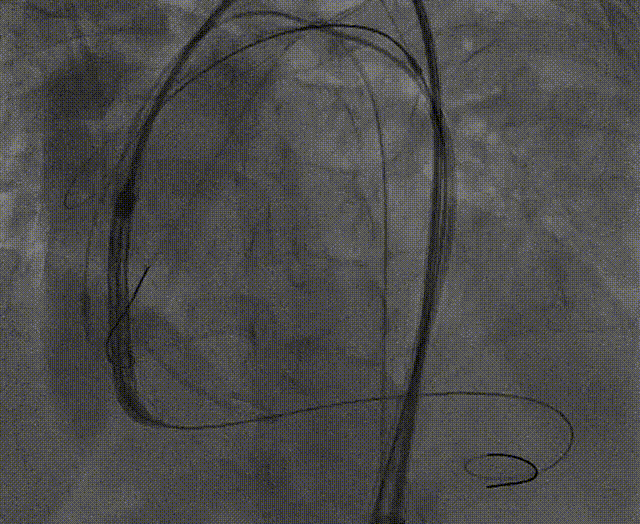

手术开始后,彭小平、姜宇等专家使用猪尾导管在主动脉弓造影辅助下选定TriGUARD3™锚定区,确认释放位置,经由左股动脉送入脑保护装置,使脑保护装置完全覆盖头臂干动脉、左颈总动脉、左锁骨下动脉开口。

TriGUARD3™ 定位

TriGUARD3™ 释放过程